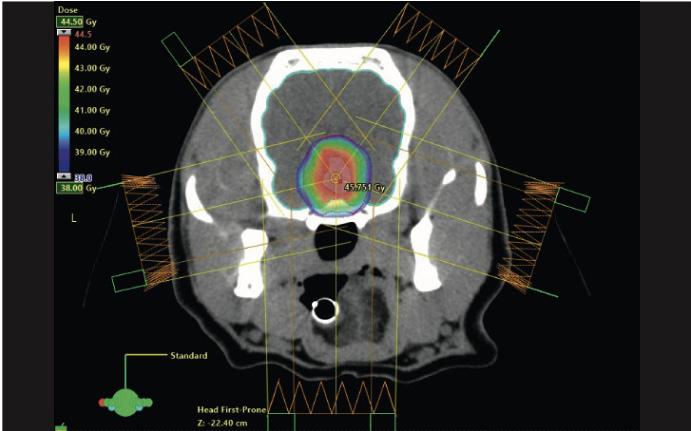

View of a radiation plan of two patients with pituitary tumors. The image at the top shows a regular irradiation protocol with a mean dose of 10x4 Gy; the image at the bottom shows the “boost” dose in the tumor center mentioned in the text with 15 percent more dose.